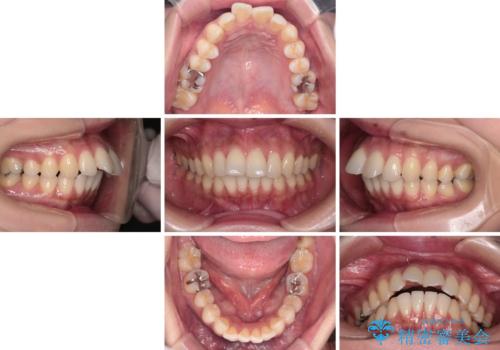

上顎前歯の突出を軽減 インビザラインによる抜歯矯正

- 上の前歯の突出感を気にして来院された患者様です。

目立たない装置を希望とのことで、上顎左右第一小臼歯を抜歯し、インビザラインにて矯正治療を行うこととしました。